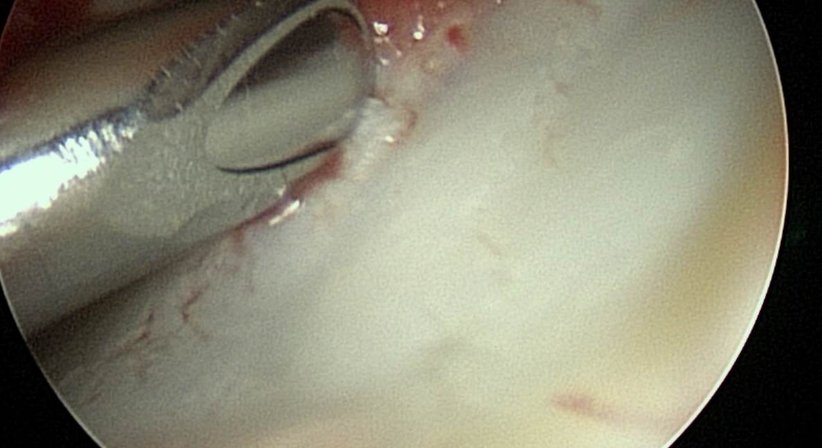

Die Handgelenksspiegelung mit sehr kleinen optische Instrumenten ist eine ideale Methode zur Beurteilung von Knorpel – und Bandstrukturen im Handgelenk, speziell bei therapieresistenten Beschwerden, die mittels MRT Untersuchung nicht zufriedenstellend abgeklärt werden konnten.

Mit keiner Methode können Instabilitäten der Handwurzel und Knorpelschäden genauer beurteilt werden. Die Handgelenksarthroskopie ist daher wichtiger Teil zur Entscheidungsfindung vor offenen Handgelenksoperationen, ist aber auch als eigenständiger Eingriff bei passender Indikation sehr erfolgversprechend.

Dabei handelt es sich um eine Schädigung des Aufhängeapparates der Elle an der Speiche im Handgelenk, die durch eine akute Verletzung oder degenerativ z.B. durch eine überlange Elle im Handgelenk entstehen kann. Die Handgelenksarthroskopie erlaubt sowohl die genaue Untersuchung des TFCC als auch die Therapie der Veränderung.

Rißbildungen der Knorpelscheibe bzw. Abrisse der Aufhängung an der Elle können mittlerweile durch spezielle chirurgische Instrumente sehr elegant durch kleine Hautschnitte und ohne Schädigung der Handgelenkskapsel genäht werden.

Die Handgelenksarthroskopie bietet heute die Möglichkeit, die Knorpelschäden im Handgelenk und der Handwurzel genau zu diagnostizieren und anschließend auch nur die Gelenksteile zu versteifen, die vom Knorpelschaden betroffen sind und jene zu erhalten, die noch über einen gesunden Gelenksknorpel verfügen.